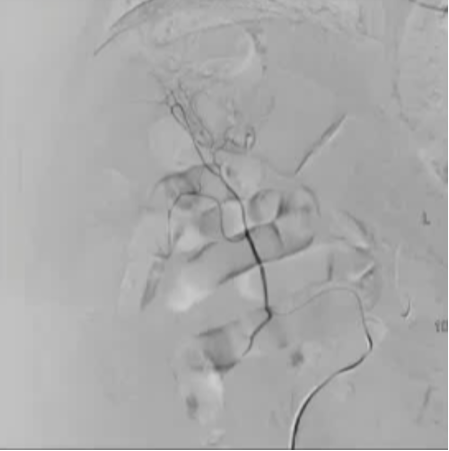

病例1 70/40 mmHg

病例1 20μg Arterenol (去甲肾上腺素) 155/85mmHg

|

激发下 |

栓塞后 |

病例二

20 μց Arterenol 170/80 mmHg

病例3 80/50 mmHg

40 μg Arterenol 170/90mmHg

出血点, |

PVA栓塞 |